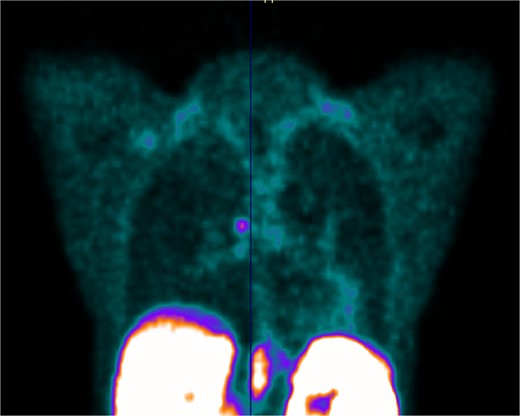

Her case was discussed at our lung cancer multidisciplinary meeting; the biopsy confirmed a carcinoid tumour with no atypical features and the recommendation was for a DOTATATE PET (Fig. 4).

PET scan showing DOTATATE uptake at the level of the right main bronchus; there was no evidence of DOTATATE avid nodal or metastatic disease.